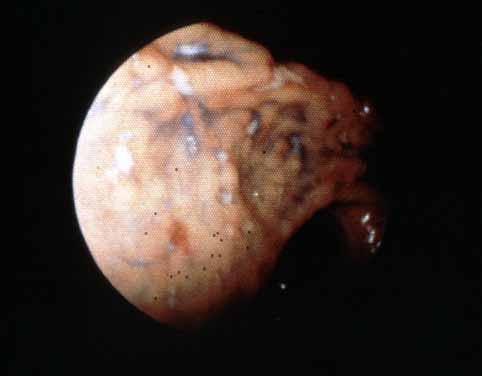

食道、胃、十二指腸に微小・微細病変を伴った小腸Crohn病の1例の胃の内視鏡像  胃の色素内視鏡写真で、胃角部から前庭部を中心にみた像です。色素の散布によって、病変がよくわかるようになっています。大きさが数mm大で、形が不整形の白苔を有する潰瘍(アフトイド潰瘍)が多発しています。

疾患(病理主体)の分類炎症性・潰瘍性疾患/クローン病

部位(臓器別)胃(部位)/胃角

検査方法内視鏡

病変の最大径(ミリ)1〜9